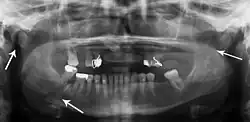

Plain film radiography

Traditionally, plain films of the mandible would be exposed but had lower sensitivity and specificity owing to overlap of structures. Views included AP (for parasymphsis), lateral oblique (body, ramus, angle, coronoid process) and Towne's (condyle) views. Condylar fractures can be especially difficult to identify, depending on the direction of condylar displacement or dislocation so multiple views of it are usually examined with two views at perpendicular angles.[11]

lateral oblique image demonstrating a fractured mandible.

Towne's view of a bilateral condyle fracture. White arrow is a fracture on the neck of the condyle. Black arrow shows the condyle pulled to the medial. The same injury can be seen on the opposite side -